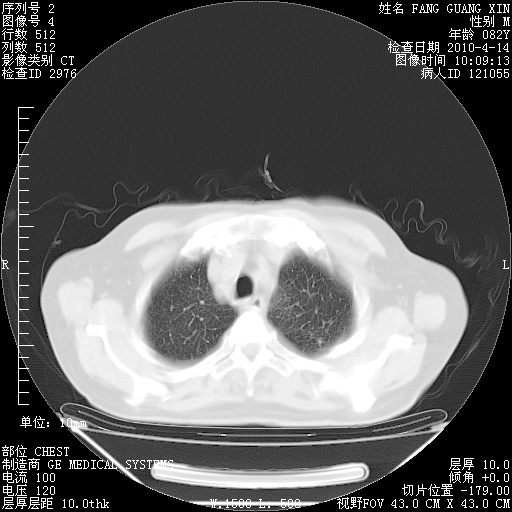

4月14日肺部CT

楼主| 发表于 2010-4-28 16:51 | 显示全部楼层

楼主| 发表于 2010-4-28 16:53 | 显示全部楼层

肺部CT平扫未见异常。